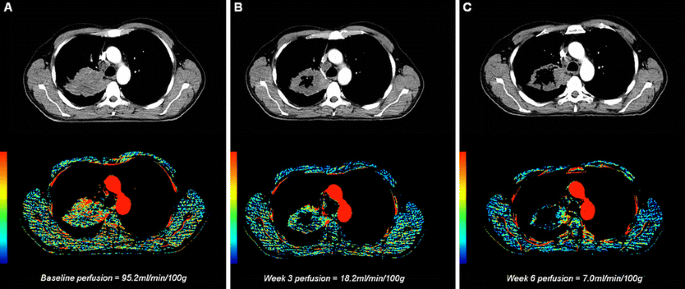

An example of serial DCE-CT and perfusion parameter maps of the thorax (axial plane) of a study patient. a Tumour blood flow at baseline was 95.2 ml/100 g/min. b After 3 weeks of treatment tumour cavitation was present and the blood flow had decreased to 18.2 ml/100 g/min. c After 6 weeks there was more extensive tumour cavitation. Blood flow in the remaining peripheral tumour tissue had decreased to 7.0 ml/100 g/min

There was a wide variation in baseline BF, ranging from 10.5 to 125.0 ml/100 g/min but mean BF values did not differ between the two centres. Mean baseline BF was 39.2 ± 29.9 ml/100 g/min. After starting treatment, BF decreased in all but one patient after 3 weeks (this patient showed a subsequent decrease in BF at week 6) and all except one patient after 6 weeks (this patient had an initial decrease at week 3) compared with baseline. An example is shown in Fig. 1. The mean perfusion decreased significantly to 15.1 ± 16.5 ml/100 g/min (range 0 to 60.0 ml/100 g/min; p < 0.001) at week 3 with a mean decrease of 60 ± 37% (range −100 to +7%) and to 9.4 ± 15.4 ml/100 g/min (range 0 to 66.4 ml/100 g/min; p < 0.001) at week 6 with a mean decrease of 72 ± 35% (range −100 to +18%) compared with baseline (Fig. 2). As a result of extensive necrosis and/or cavitation of the primary tumour, BF was not measurable in seven patients at week 3 and nine patients at week 6, and was recorded as being zero. Baseline BF was lower in patients who developed extensive cavitations (31.2 ± 21.0 ml/100 g/min) compared with those who did not (50.0 ± 35.2 ml/100 g/min), p = 0.012.